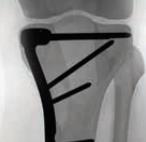

Proximal Tibia Fracture System

• The Proximal Tibia Fracture System is a comprehensive plating set designed for treatment of a variety of tibial plateau fractures.

• The system features three styles of Lateral Proximal Tibia Plates, a Medial Locking Plate, and a Posteromedial Buttress Plate to address intra-articular and extra-articular fractures of the proximal tibia.